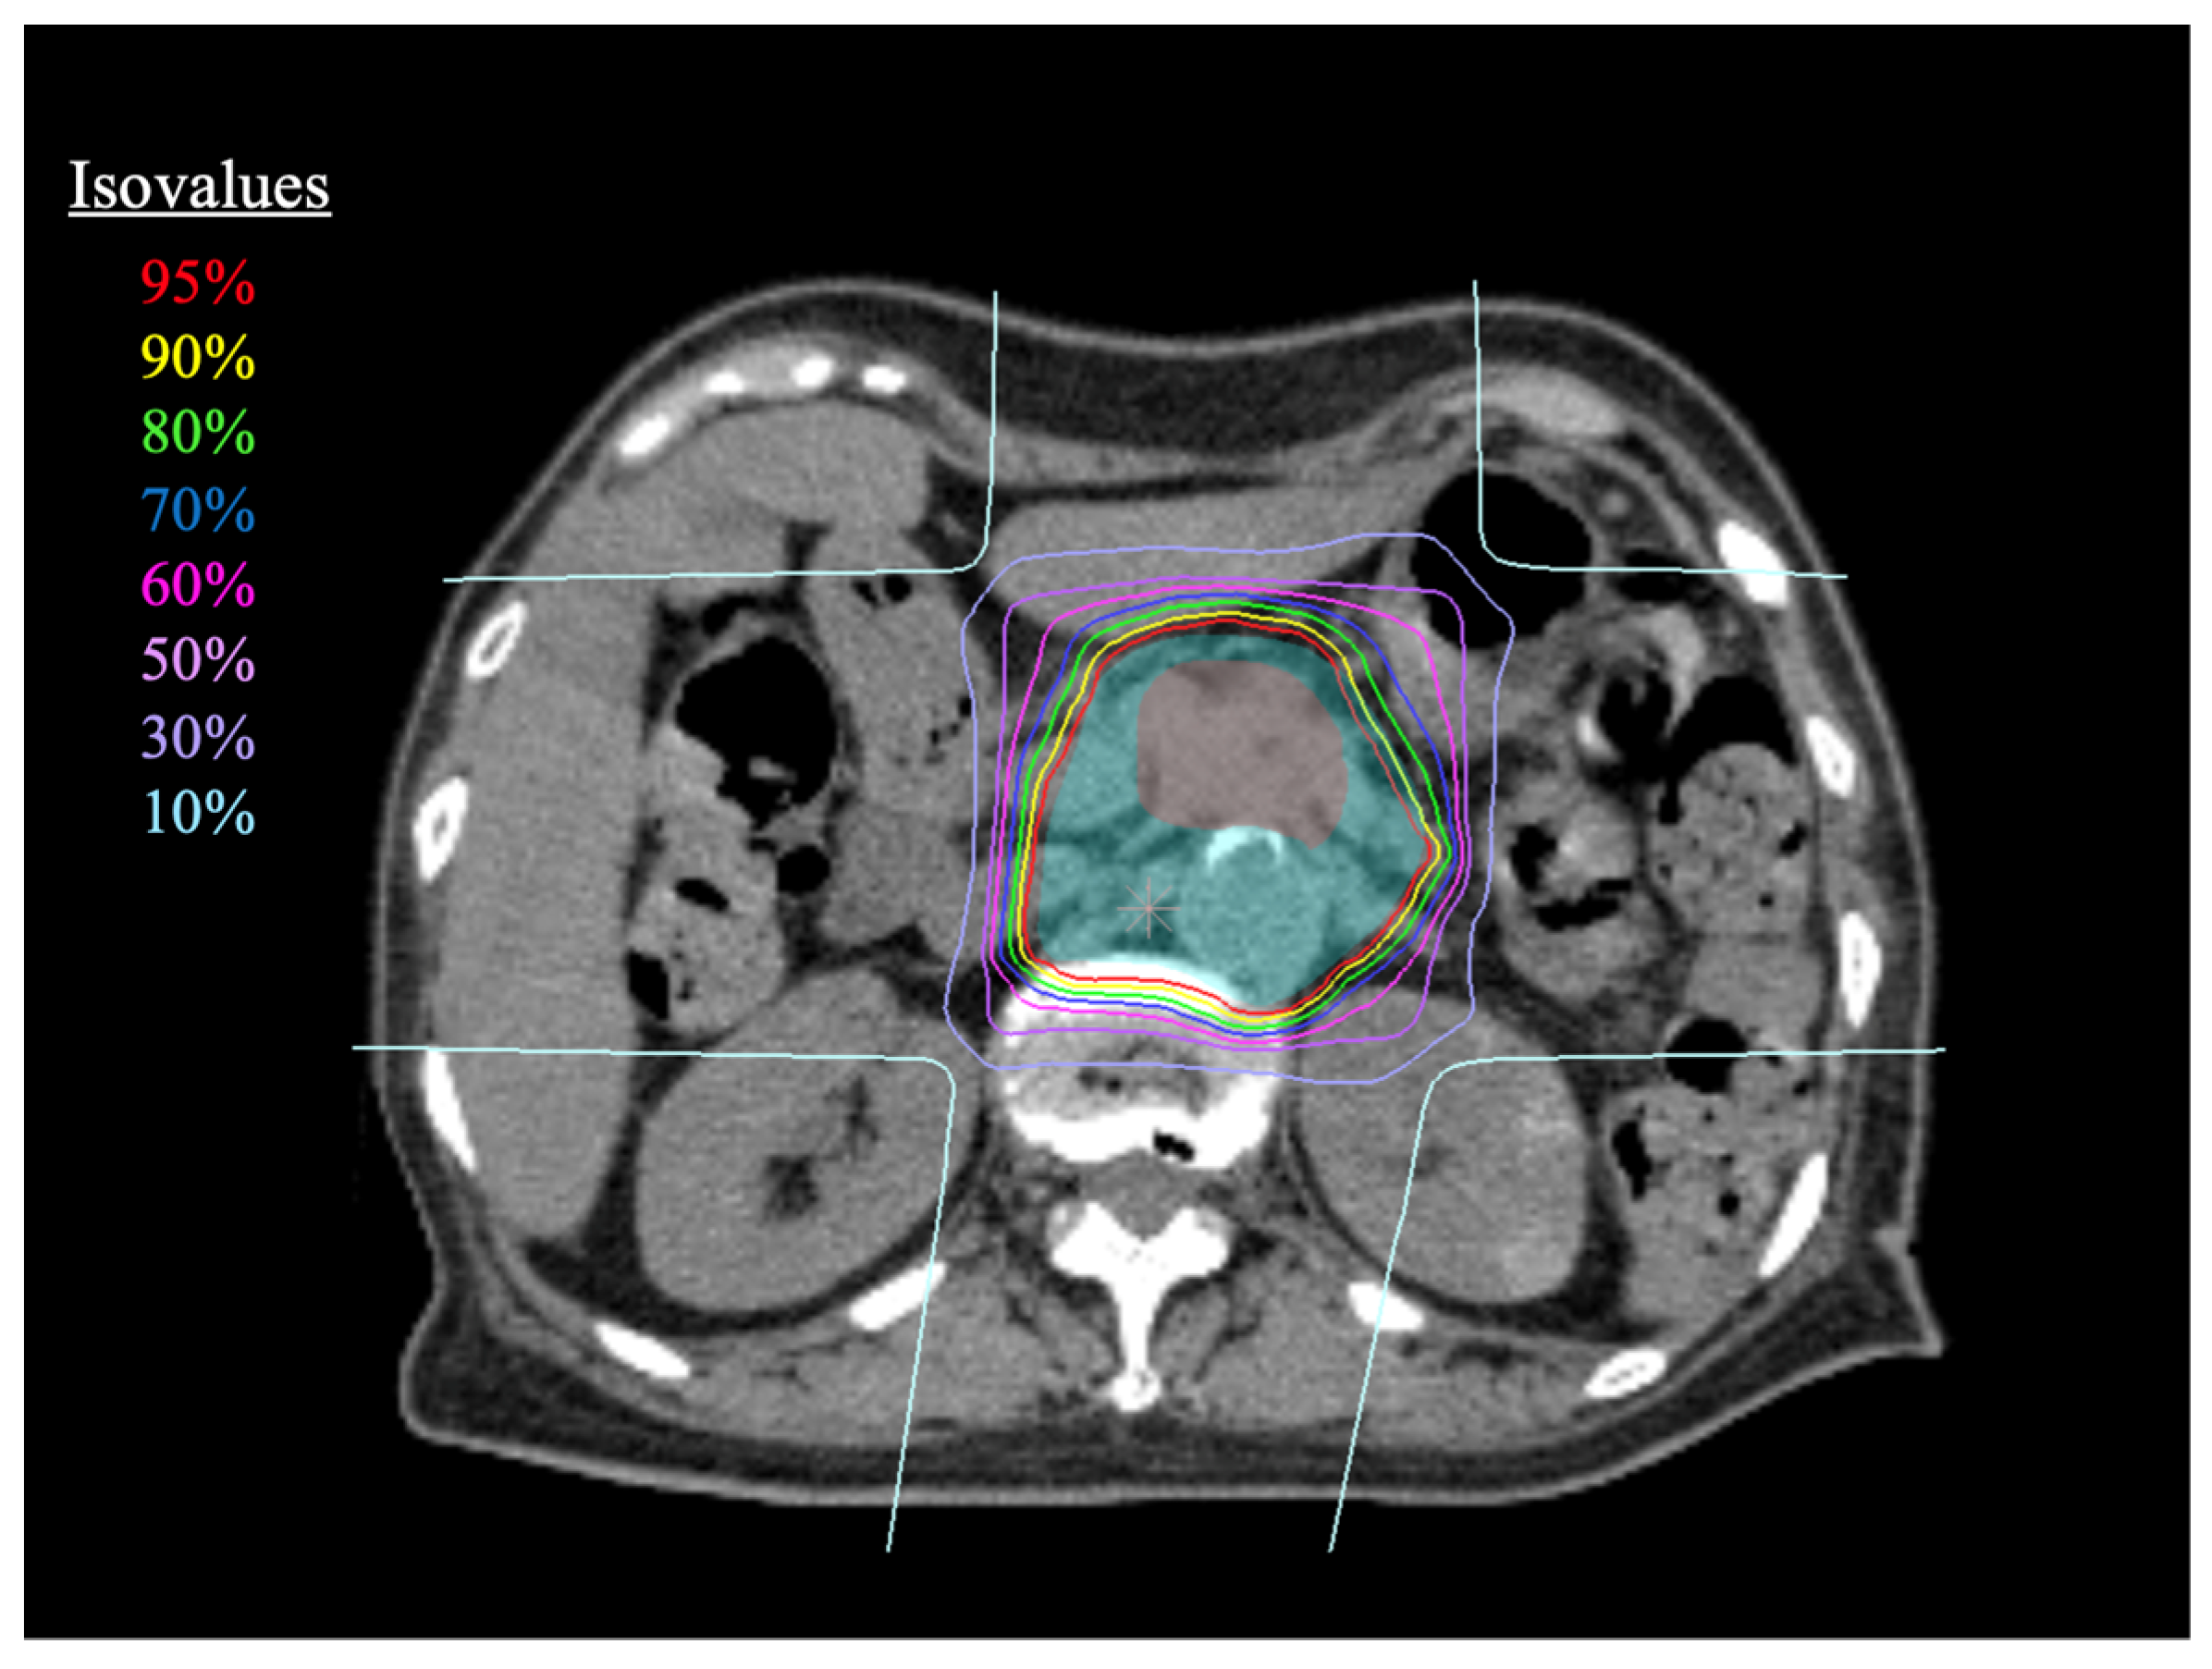

2.2. Carbon-Ion Radiotherapy

2.3. Treatment Planning